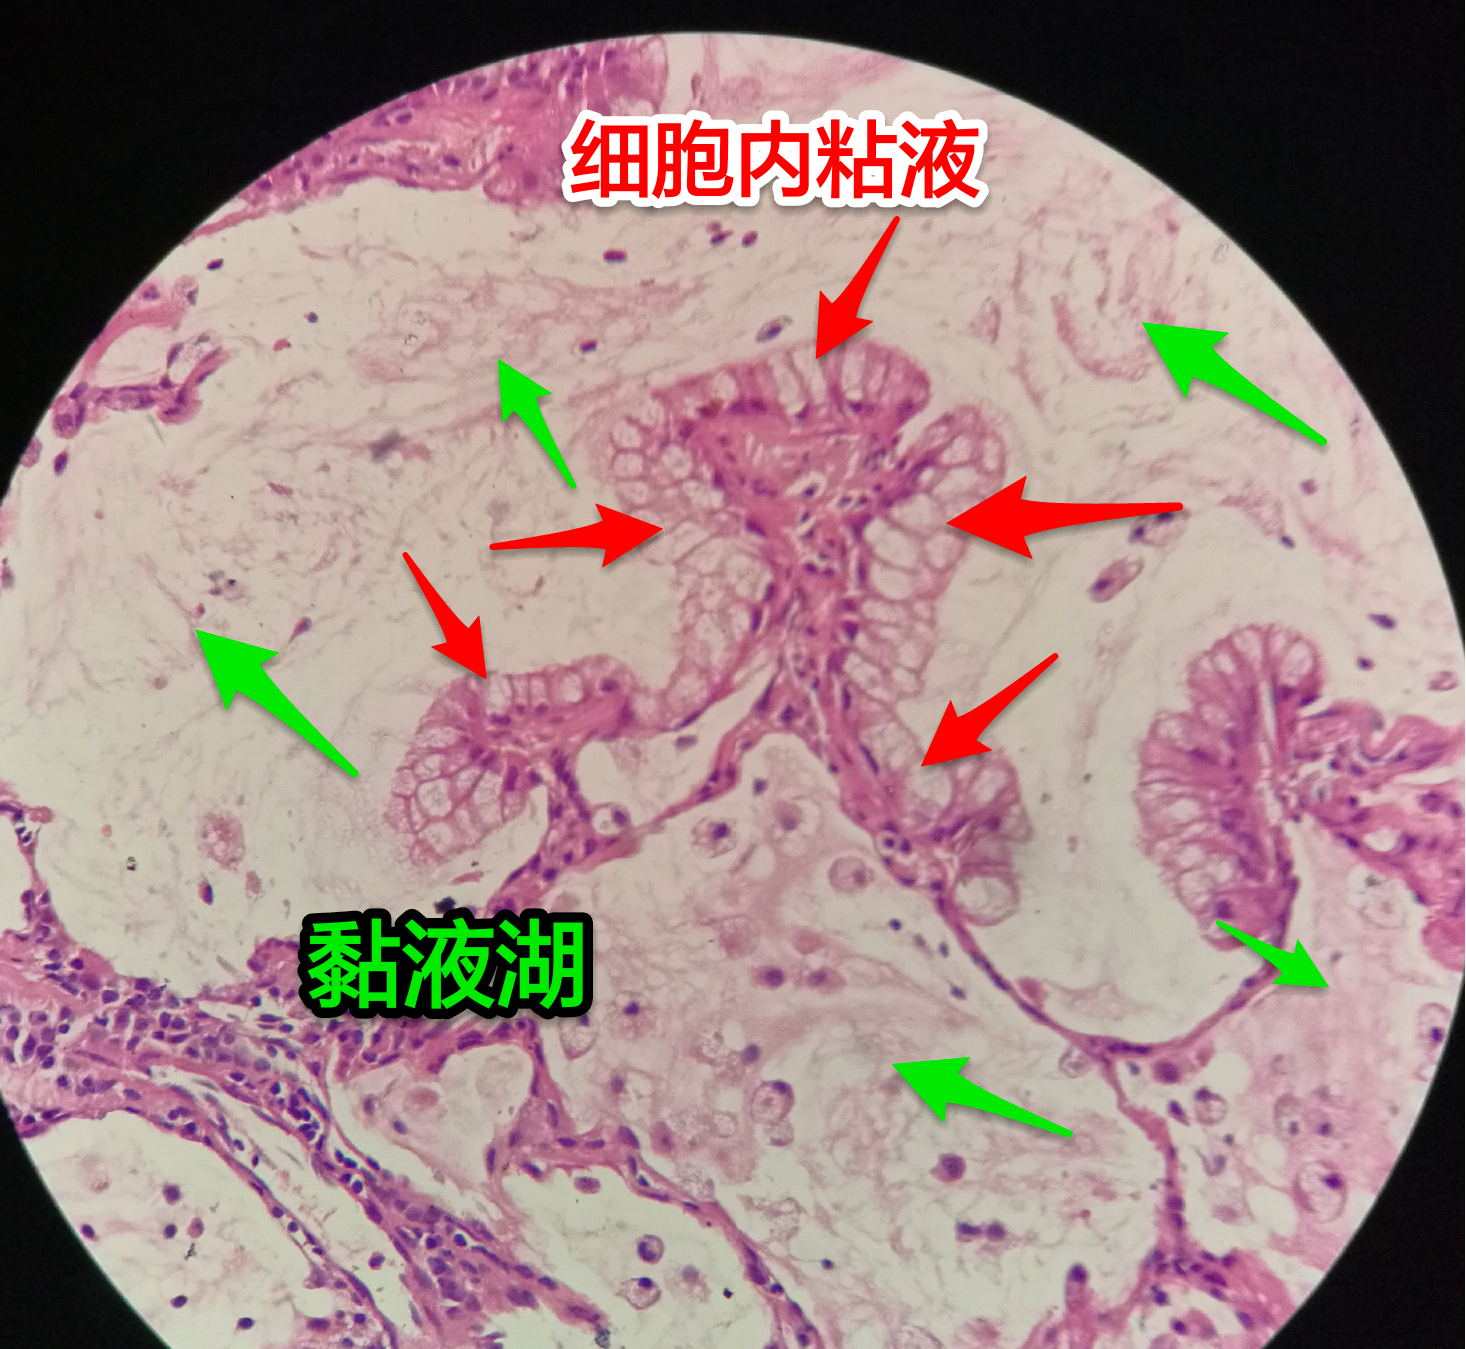

粘液型腺癌

粘液型腺癌是原发肺腺癌中的一种特殊类型

细胞内外含较多粘液

粘液型腺癌,细胞内粘液多,有点儿像支气管的粘液腺

单纯的粘液腺,没有浆液腺

细胞外粘液湖

粘液腺癌起源于细支气管和肺泡

细胞外粘液是白色偏微红

这一幅的上方都是黏液湖

下方是正常肺泡

细胞内白颜色区是粘液,细胞外洋流样的也是粘液(湖)

黏液湖里可以飘着一些细胞,吞噬细胞及肿瘤细胞。

肿瘤细胞飘出去可以种植于肺泡上。

肿瘤细胞堆经常是离开的

中间这一团,整个都是飘过来种植长成这样

粘液型腺癌的肿瘤细胞排列整齐,核位于基底,细胞呈柱状。

肺泡间隔(间质)经常比较细